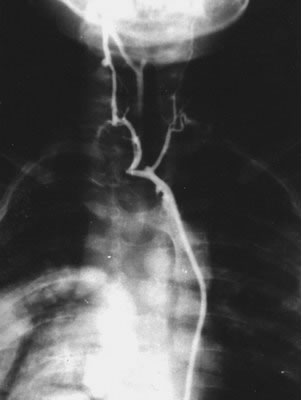

- Трансфеморальная катетеризация венозного щитовидного

сплетения с суперселективным взятием образцов крови для

определения концентрации паратиреоидного гормона, кальцитонина

и пролактина

Продемонстрирована методика выполнения суперселективной

катетеризации венозного щитовидного сплетения.